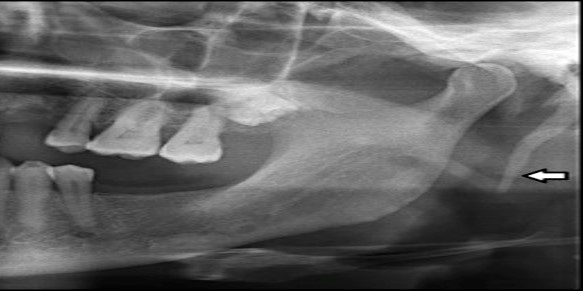

1) Identify the asymptomatic radiopacity indicated by the arrows. Patient was 65 years old and suffered from Diabetes and hypertension.